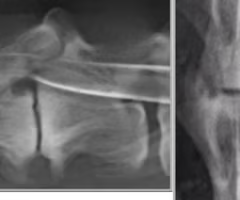

What are risks of a myelogram?

Invasive

Seizures

-CT/MRI replaced

Where do we give contrast medium?

Subarachnoid space at L5-L6 b/c spinal cord has ended here

Identify the pathology?

Extradural

Intramedullary

What are two signs of intradural extra medullary?

Golf tee sign -widening subarachnoid

Filling defect

Intradural extra medullary